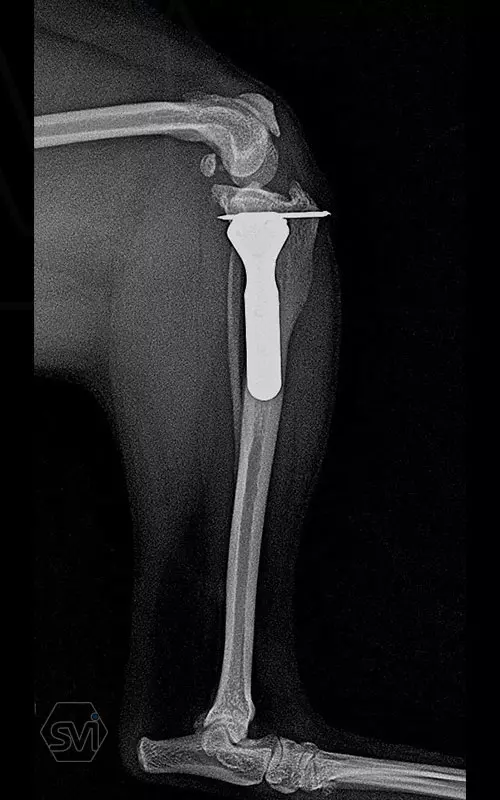

The attached x-rays were taken during the check-up of a 6.5-year-old Yorkshire terrier that underwent TPLO-M surgery a year and a half ago, the limb is fully loaded, it shows no lameness, the osteotomized parts are well ossified, the bone stock has not been resorbed.

A mellékelt képek egy másfél évvel ezelőtt TPLO-M műtéten átesett, most 6,5 éves yorkshire terrier kontrollja során készült, a végtagot teljesen terheli, sántaságot nem mutat, az oszteotomizált részek jól csontosodtak, a csontállomány nem szívódott fel.